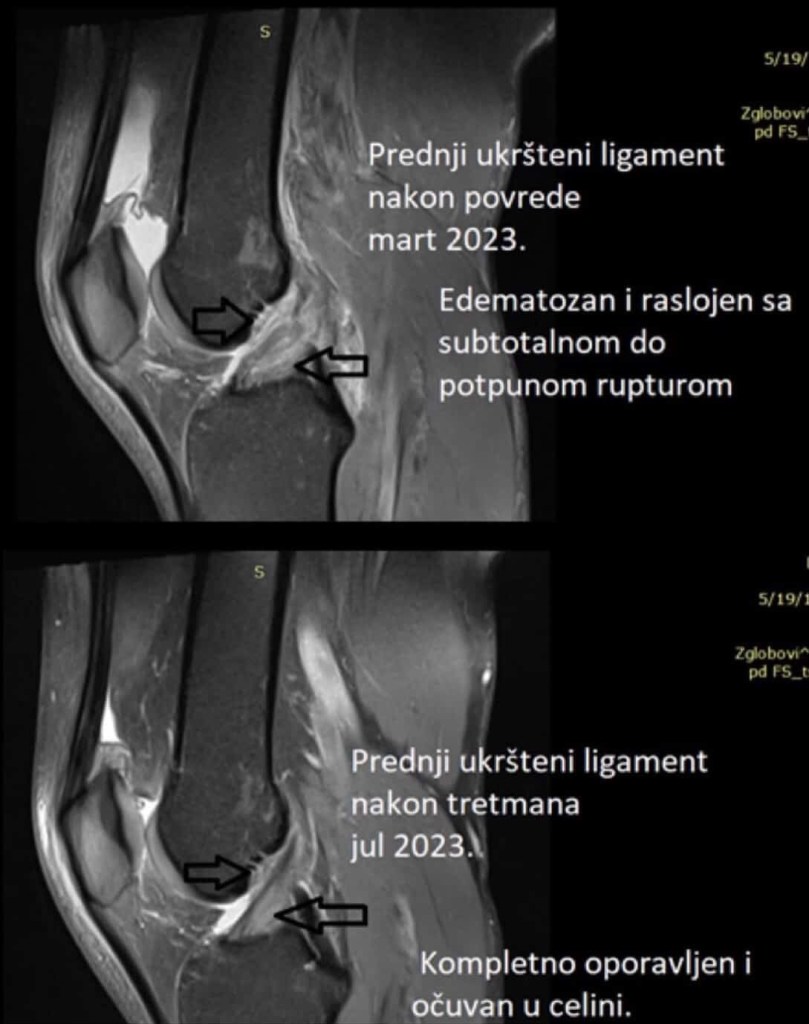

Recently, I’ve seen another powerful case in the clinic: a healed ACL without following a brace protocol — the second time I’ve witnessed this.

After I posting about my case, I have say thanks to @fitfizio for sharing his own experience as he reached out with a patient who had a healed ACL in just 4 months.

Also a newly reported case from Australia reported healed ACL at 3 months follow up. Link